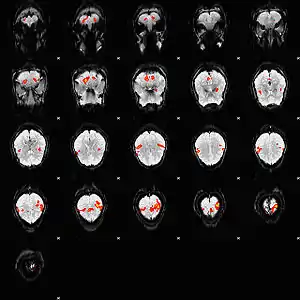

تصویربرداری کارکردی BOLD یا تصویربرداری کارکردی وابسته به میزان اکسیژن خون (به انگلیسی: Blood Oxygenation Level Dependent fMRI) یا به اختصار BOLD fMRI، نوعی روش تصویربرداری در اف ام آر آی است.

این روش کارکردی (fuctional) بر پایه مکانیسم تأمین انرژی نورونهای فعال به صورت افزایش سطح اکسیژن خون (خونرسانی) در نواحی فعالیت بنیان گذاشته شدهاست. فعالیت نورونها همراه با صرف انرژی است که از طریق واکنشهای هوازی تأمین میگردد. اکسیژن موردنیاز این واکنشها را اکسی هموگلوبینها در خون حمل و برای انتقال به نورونها منتقل میکنند. به این ترتیب، افزایش فعالیت نورونها همراه با افزایش تعداد اکسی هموگلوبینها و بعبارتی افزایش سطح اکسیژن خون است. اندازهگیری میزان افزایش سطح اکسیژن در خون با در نظر گرفتن اختلاف پذیرفتاری مغناطیسی بین اکسی هموگلوبین و دی اکسی هموگلوبین ممکن است که به افزایش سیگنال در این نواحی به عنوان نواحی فعال مغزی می انجامد.[1][2]>